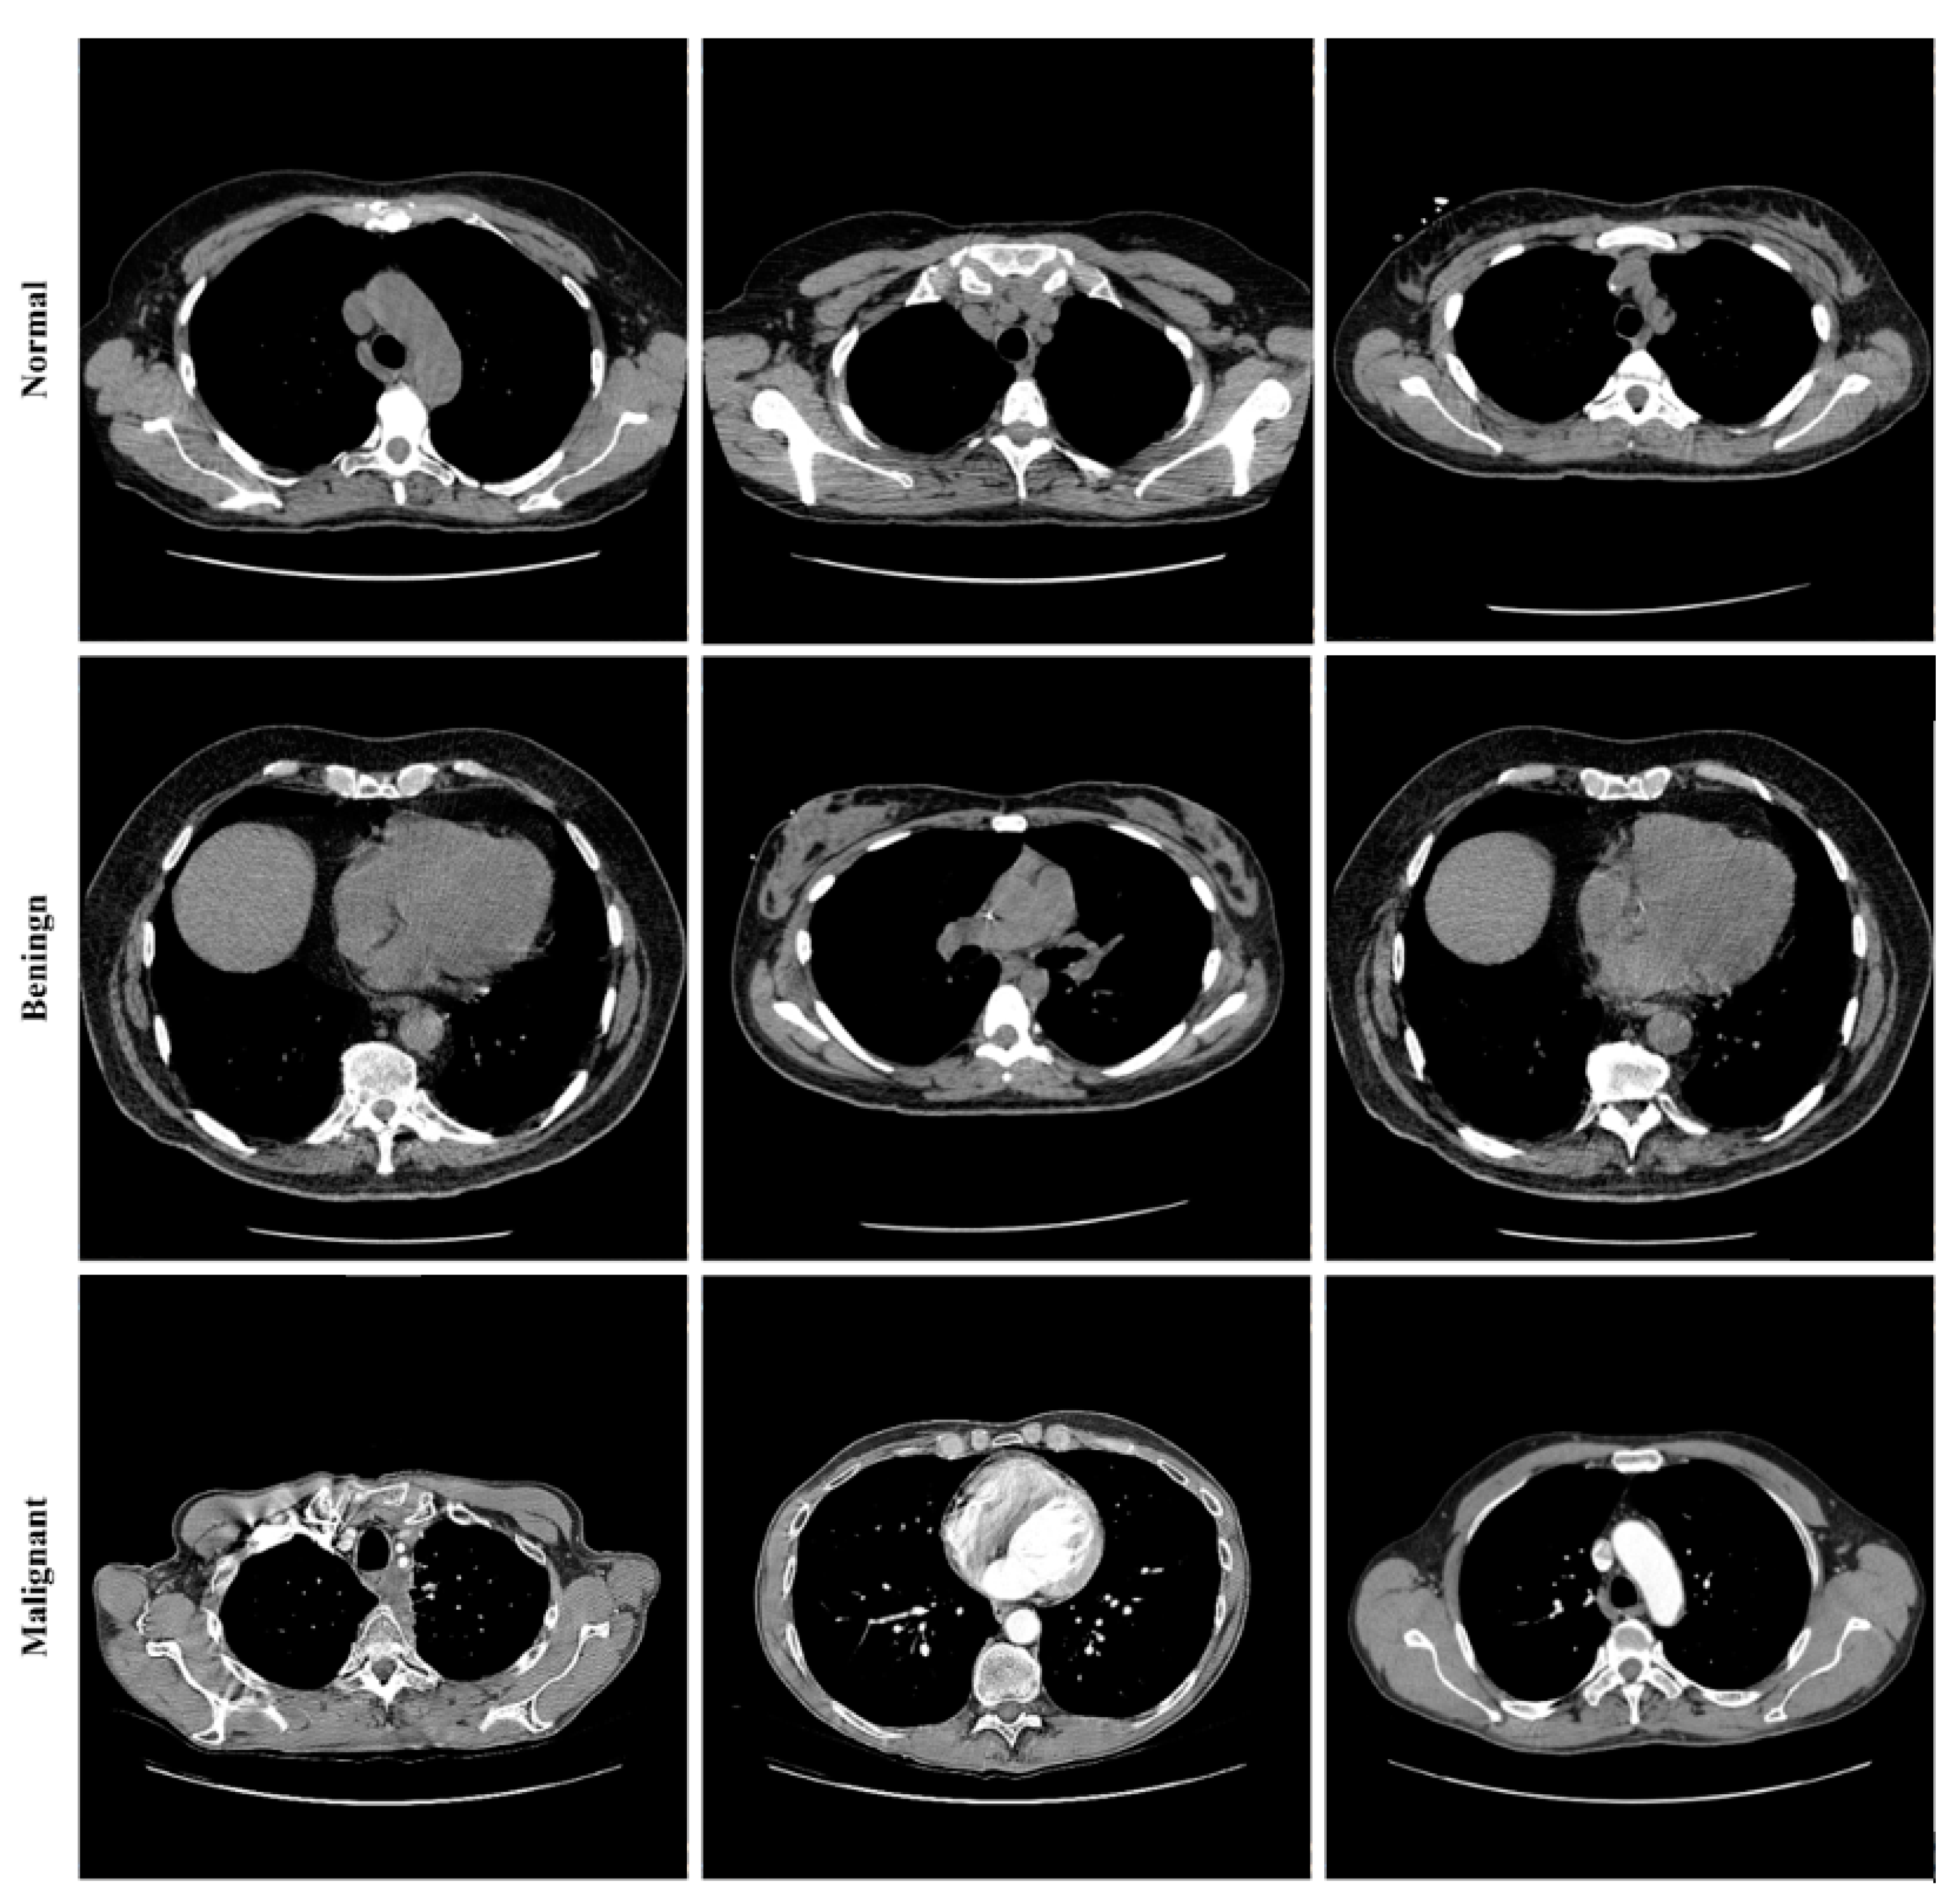

Lung cancer categorization may use a wide variety of currently accessible datasets. Lung Image Database Consortium Image Collection (LIDC-IDRI) [], Luna16 [], and NDSB3 (Neural Data Standardization Board, Version 3), were some of the datasets available []. It is possible to acquire images, analyze them, segment them, extract features from them, and classify them all with the help of a CAD system. For a CAD system to be constructed, it is necessary first to pre-process the datasets used in the project. This study used data from the LIDC-IDRI []. There were 910 photos utilized; 250, 320, 320 as normal, benign, and malignant, respectively. The RGB pictures were 512 pixels by 512 pixels in size. Lung cancer screening and diagnosing thoracic CT images with identified lesions made up the LIDC-IDRI. This dataset was compiled by the combined efforts of eight medical imaging firms and seven academic institutions. The data collection was initially stored in the format for Digital Imaging and Communications in Medicine (DICOM). An intermediate dataset was created by down sampling the original data and saving it in “jpeg” format. Denoising the dataset as part of the pre-processing step allowed us to obtain even better results. Figure 8 shows some images from the dataset.

Figure 8.

Sample images from the LIDC-IDRI dataset.